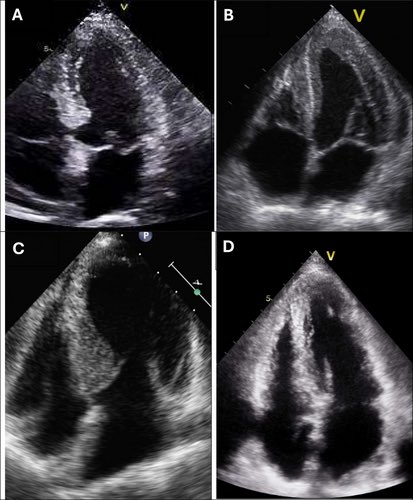

Echocardiographic Features of Cardiomyopathies: A Comprehensive Review doi.org/10.1111/echo.7… #Echofirst #iecho #cadiology #echofirst #CardioEd

Echocardiographic Features of Cardiomyopathies: A Comprehensive Review

doi.org/10.1111/echo.7…  #Echofirst #iecho #cadiology #echofirst #CardioEd